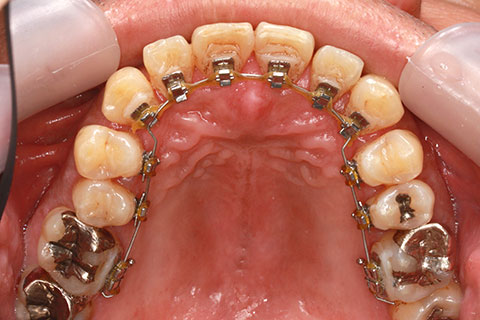

治療前

治療中(開始直後)